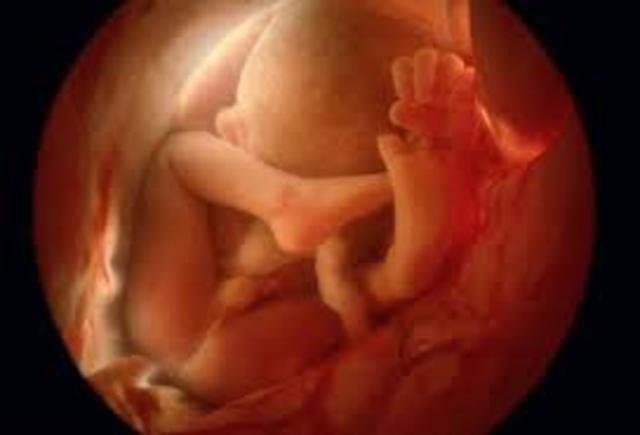

• Week 20

Week 20

The fetus is around 21 cm in length. The ears are fully functioning and can hear muffled sounds from the outside world. The fingertips have prints.